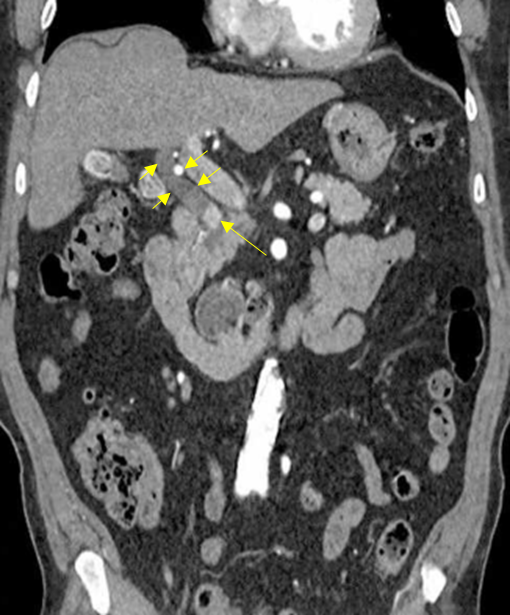

65세 남자가 2시간 전부터 윗배가 아파서 병원에 왔다. 혈압 100/60 mmHg, 맥박 111회/분, 호흡 20회/분, 체온 37.9℃이다. 공막에 황달이 보인다. 오른쪽 윗배에 압통이 있으나 반동 압통은 없다. 혈액검사 결과는 다음과 같다. 복부 컴퓨터 단층촬영 사진이다. 치료는?

Img | CT: CBD dilatation, r/o CBD stone |

Distal CBD obstruction이 확인되므로 보기 중 ENBD를 고려할 수 있다.

• CT상 proximal CBD dilatation이 보이므로, distal CBD obstruction이 발생했음을 알 수 있다. Obstruction의 원인이 stone인지 tumor인지는 CT 단면 1개로는 파악하기 다소 어려우나(CT에서 고음영으로 보이므로 CBD stone일 가능성이 상대적으로 높다), biliary drainage가 필요하다는 것은 명백하다.